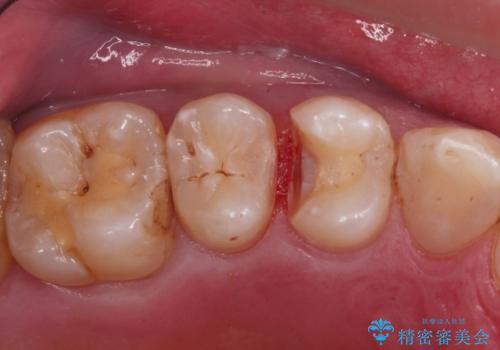

歯と歯の間の虫歯(コンタクトカリエス)

- 虫歯がないかチェックしてほしいとの事で来院。

レントゲンで歯と歯の間に虫歯(コンタクトカリエス)があったので

拡大鏡下で虫歯を全て除去して、e-maxインレーにて治療しました。